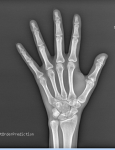

Открыты ли зоны роста, девушка, 18 лет?

Здравствуйте, Можете пожалуйста оценить открыты ли еще зоны роста? В дествте была одной из самых высоких в классе, в подростковом возрасте что-то рост сильно замедлился